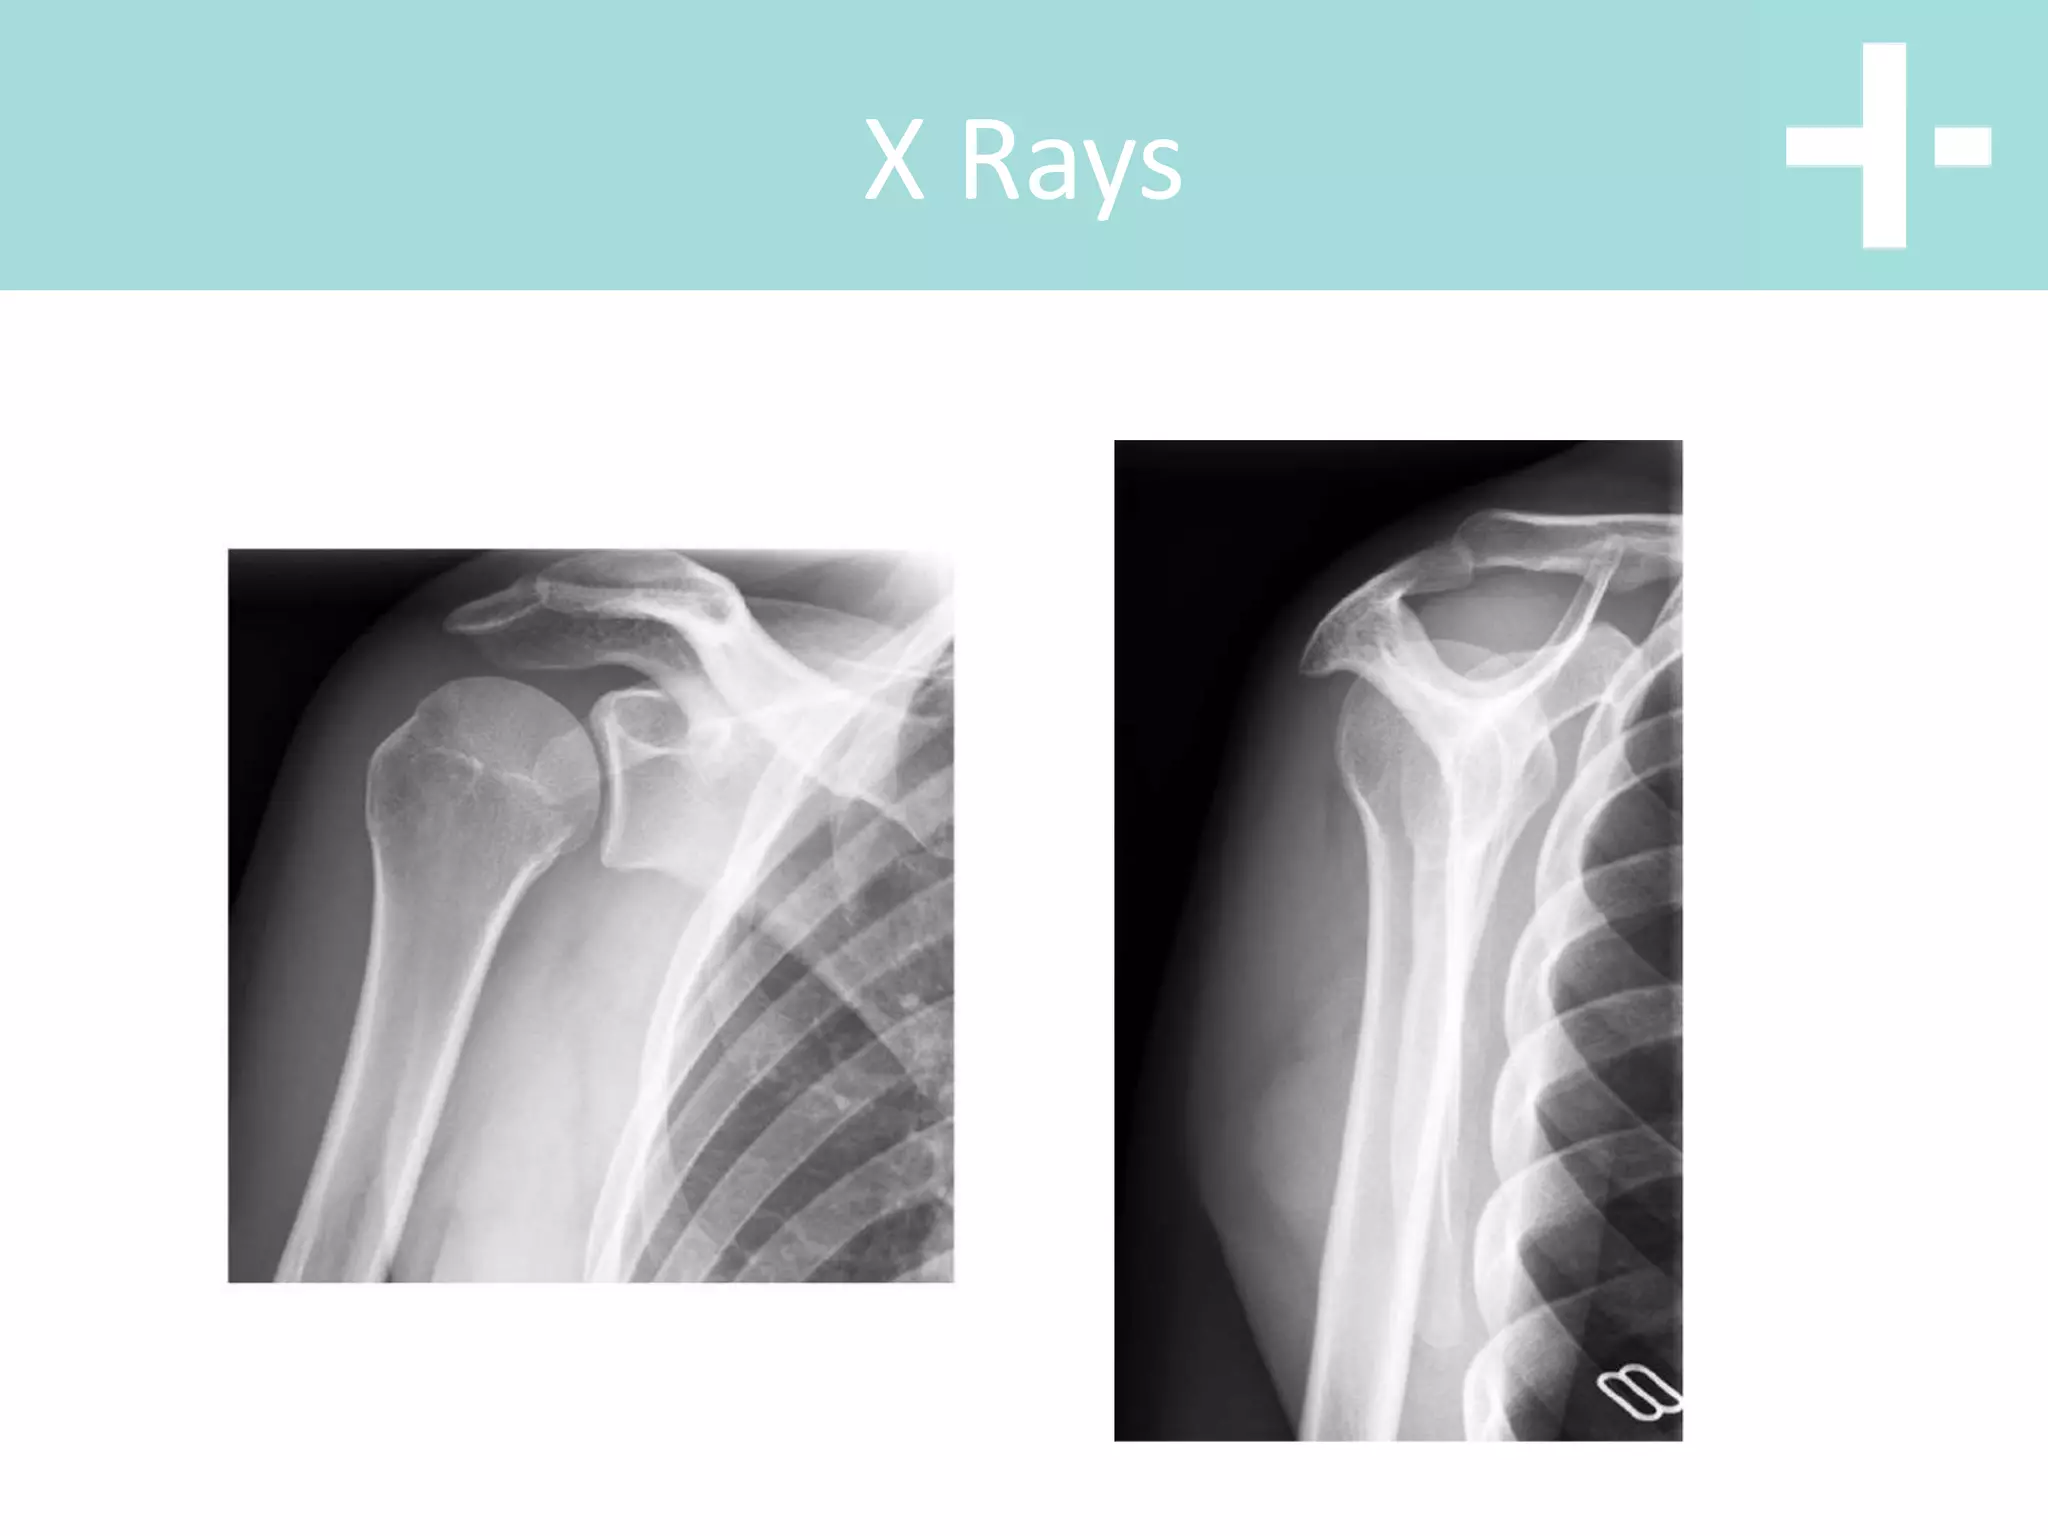

X Rays

Axillary Lateral

Anterior Dislocation